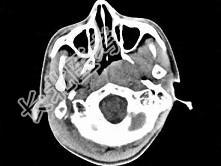

- 单项选择题男,17岁, 自诉鼻涕中带血3个月,伴耳闷、听力减退, 无发热。如图所示鼻咽部病灶最可能的诊断为 ( )

C、鼻咽癌